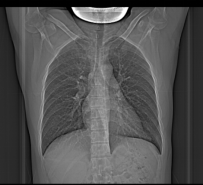

近日,北京积水潭医院贵州医院接诊了一位特殊的患者。他正值壮年,没有遭遇过严重撞击或外伤,却在两个月内接连发生肋骨骨折:一次是双手举小孩后左胸痛,一次是切菜后右胸痛。检查发现,他存在多处肋骨骨折,且胸腰椎骨骼也出现了弥漫性的异常信号。

这种在轻微外力甚至日常活动中发生的骨折,医学上常被称为“病理性骨折”或“脆性骨折”,意味着骨骼本身的强度已经严重下降,如同被蛀空的木头,稍一受力就会断裂。

那么,是什么原因导致该壮年的骨骼变得如此“脆弱”呢?完善相关检查后,最后发现,他居然是患了一种血液系统疾病:多发性骨髓瘤!